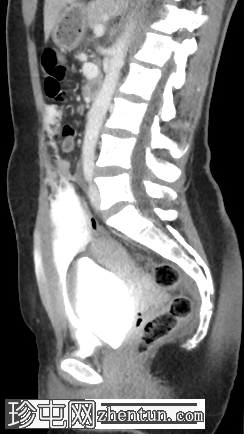

矢状位增强扫描(门静脉期)

膀胱腹侧黏膜全层缺损,造影剂显影的尿液活动性外渗至盆腔。造影剂似乎局限于腹侧筋膜间隙。一条线状造影剂显影的尿液穿过下腹壁,位于腹直肌鞘内。

这是一例腹膜外膀胱破裂。